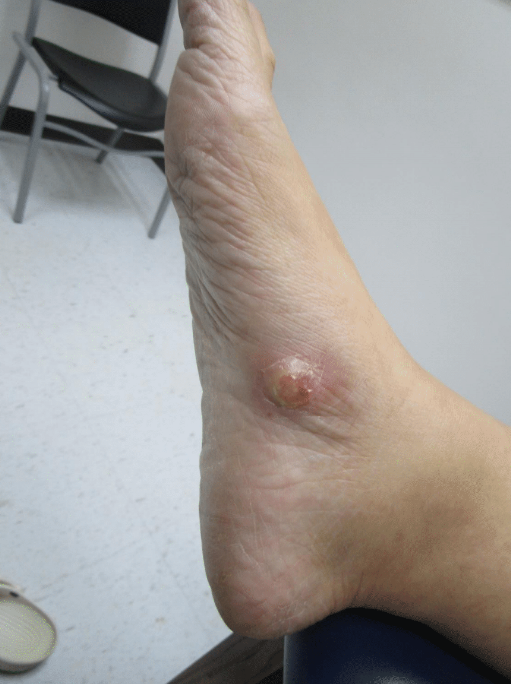

CHIEF COMPLAINT: “I have a painful bump growing on my foot”

CLINICAL HISTORY: A 40-year-old female with a medical history of anemia and hypothyroidism presented to our clinic with a two-month history of a rapidly growing, tender lesion on her right foot. The patient reported no prior trauma to the area and denied experiencing any similar lesions in the past. She also reported no discharge or itching at the site of the lesion. She reported no recent travel, exposure to sick contacts, and has no personal or family history of similar lesions or skin cancer.

Physical examination demonstrated a solitary, tender nodule on the medial aspect of the right foot. Popliteal lymph nodes on the right lower extremity were slightly palpable but similar in comparison to the left side. There were no palpable inguinal lymph nodes.